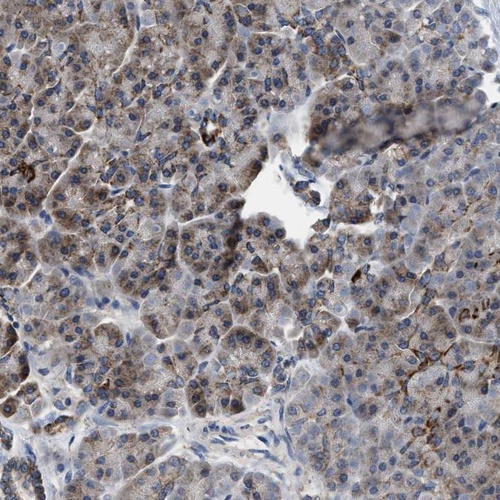

Immunohistochemistry analysis in human lymph node and pancreas tissues using Anti-CCM2 antibody. Corresponding CCM2 RNA-seq data are presented for the same tissues.